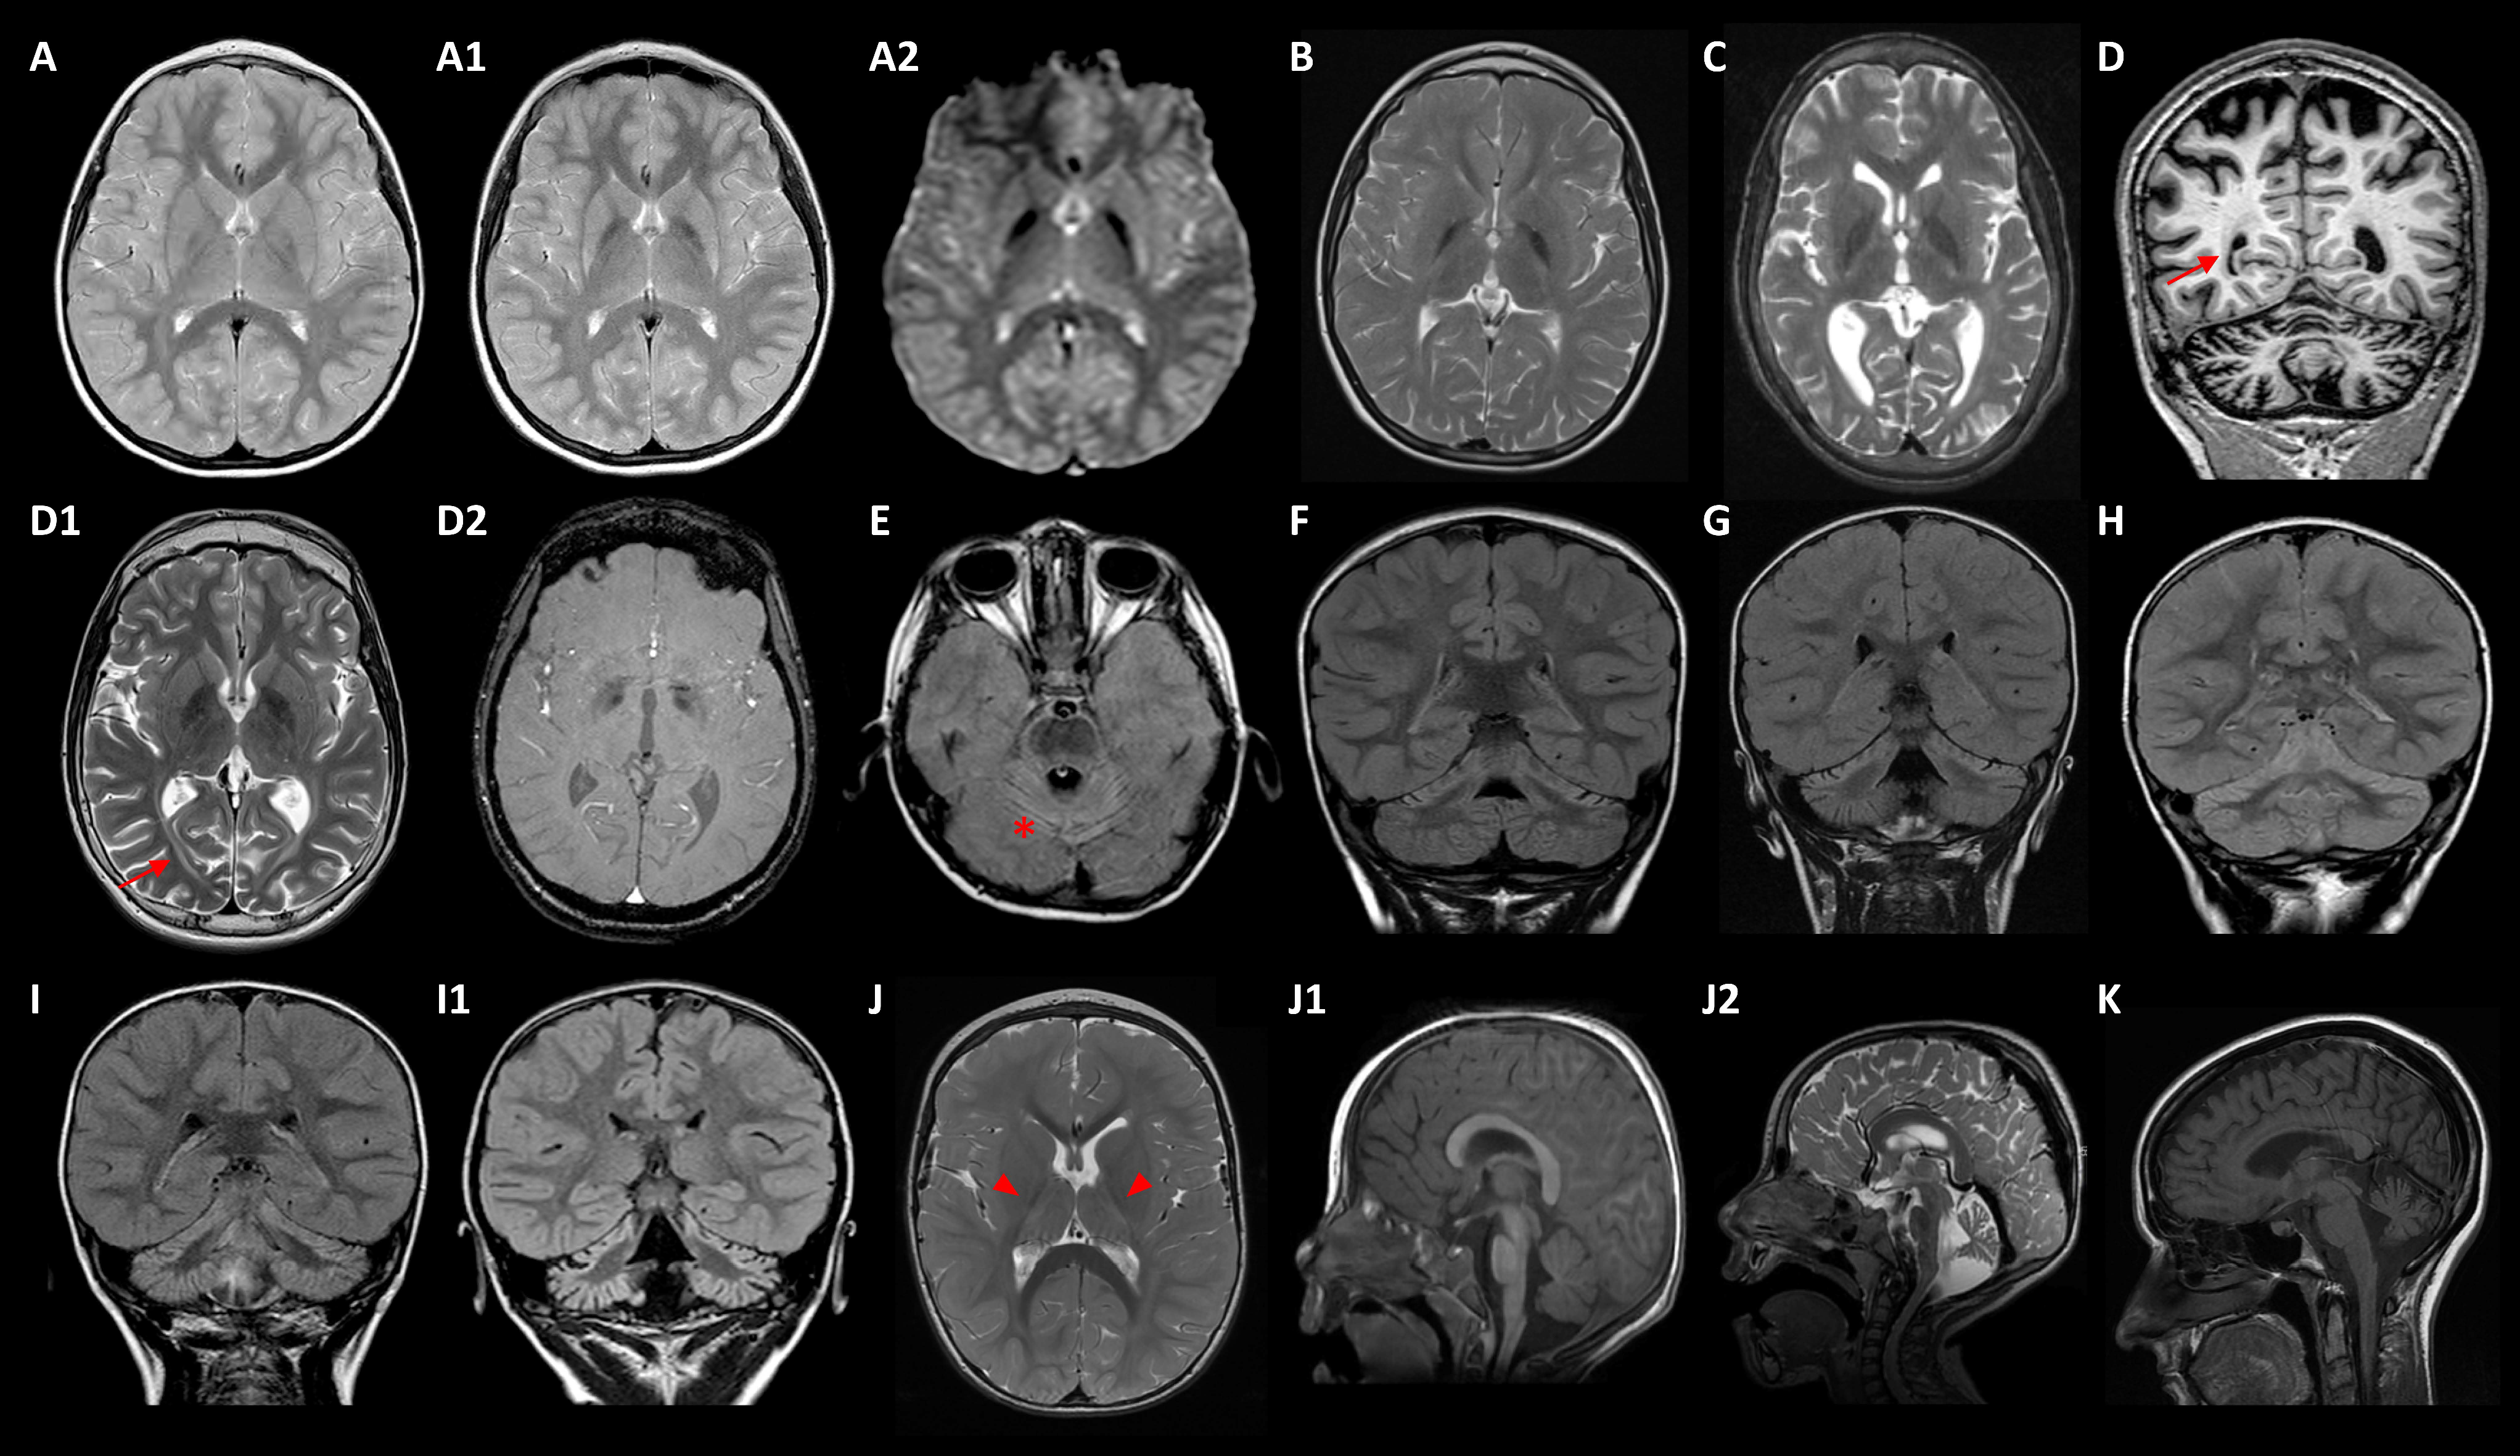

2.2. Genotype-Phenotype Correlation

Five cases with T2W MRI showing bilateral GP hypointensities carried disease-causing mutations in FBXO7, GLB1, FUCA1, TPP1, and KIF1A (Table 1 and Table 2) MD-018 (homozygous FBXO7 p.S123*) was previously described [14]. MD-020 (GLB1 p.R59H/p.Y36C) suffers from a GM1-gangliosidosis type II, with an onset at age 3 with dysphemia. The patient showed a slow progression of the motor disorder, with generalized dystonia at age 12, associated with bulbar dysfunction (dysphagia, dysarthria, dysphonia), and mild flattening of vertebral bodies with scoliosis; iron-sensitive MRI sequences showed brain iron deposits from 10 years old (Figure 2A–A2). MD-137 (homozygous FUCA1 p.R47P) with a history of static encephalopathy, had a dystonic gait from 3 years old and presented GP T2W hypointensities from 10 years old (Figure 2B). MD-153 (TPP1 p.R447H/p.G77R) suffered from a progressive spastic-dystonic gait and also, showed T2W GP hypointensities, together with CA and deep white matter subtle demyelination, at the age of 14 (Figure 2C). Finally, MD-189 (KIF1A p.R316W) presented with an ataxic-spastic gait with early-onset CA, but iron deposits ascertained by SWI sequences from 17 years old (Figure 2D–D2).

Main neuroimaging features. (A–A2) MD-020/GLB1: axial TSE (turbo spin echo) T2 weighted image at ages 6 (A) and 11 (A1) showing progression of globus pallidus (GP) hypointensities, demonstrating iron deposition in axial T2* GRE (gradient echo) image (A2) at 11 years old. (B) MD-137/FUCA1 and (C) MD-153/TPP1 revealing T2-weighted images (T2WI) GP hypointensities at ages 10 and 14, respectively. (D–D2) MD-189/KIF1A at 17 years old: coronal T1-weighted image showing cerebral and cerebellar atrophy (D), axial T2WI revealing GP hypointensity (D1) and SWI, susceptibility weighted imaging (D2) showing iron deposition; the patient also presented periventricular and deep white matter abnormal signal (arrows). (E) MD-200/KIF1A at age of 4: axial FLAIR (fluid attenuated inversion recovery) image revealing global cerebellar atrophy with cortical hyperintensity (* tram-track sign). (F–H) Coronal FLAIR images uncover predominantly upper cerebellar cortical hyperintensity in patients MD-106 at age of 3 (F), MD-041 of 4 (G), and MD-320 of 4 (H), with ITPR1 variants. (I–I1) MD-323/PMPCA: Coronal FLAIR images at 2 years old (I), and at 8 years old (I1) demonstrating progression of cerebellar atrophy with cortical hyperintensities. (J–J2) MD-181/PLEKHG2 from 2 (J,J1) to 5 years old (J2): T2WI (J) showing thalamic and posterior internal capsule hyperintensities (head arrows), and mild deep white matter hyperintensity; mid-sagittal T1 weighted image (J1) and midsagittal T2WI (J2) demonstrating progression of cerebellar atrophy. (K) MD-270/HEXA: mid-sagittal T2WI revealing cerebellar atrophy at disease onset (23 years old).

Eleven diagnosed patients manifested very early-onset ataxia and CA associated with mutations in ITPR1 (3), KIF1A (3), PLA2G6, PMPCA, SPTBN2 (2), and PRDX3 (Table 1 and Table 2). The patients with mutations in SPTBN2 or PRDX3 were previously reported [13,17]. Interestingly, nine subjects evolved to an NPCA phenotype [18]; they harboured mutations in ITPR1, KIF1A, PMPCA, and SPTBN2. Additionally, five patients with ITPR1 (2) or KIF1A (3) variants developed lower limbs spasticity over time; two children with KIF1A mutations additionally associated optic atrophy, and one of them showed the early appearance of iron deposits demonstrated by iron-sensitive sequences (Figure 2D2).

In the reported PLAN series [5], CA is universal and one-third of the patients showed cerebellar cortical hyperintensities, discovered by axial or coronal FLAIR (fluid attenuated inversion recovery) MRI sequences. Remarkably, this neuroimaging finding was also observed in seven out of nine NPCA patients (Figure 2E–I1), related to deleterious variants in KIF1A (1), ITPR1 (3), PMPCA (1), and SPTBN2 (2) [13]. MD-181 (homozygous PLEKHG2 p.T53I) showed very early-onset hypotonia, and developmental delay rapidly evolved into spastic-dystonic tetraparesis from 6 months old (Table 1 and Table 2), when subtle symmetrical T2 hyperintensities on thalami and deep white matter were detected (Figure 2J). The clinical course showed a significant deterioration with the appearance of oculomotor apraxia, peripheral neuropathy, and CA from 2 to 5 years old (Figure 2J1–J2). MD-159 (SPG7 p.A510V/p.A572V), previously reported [15,19], presented early onset multifocal dystonia with severe cranio-cervical involvement and mild CA on brain MRI. MD-270 (HEXA c.459+5G>A/c.1305C>T) started with a cerebellar syndrome at 23 years old with cognitive decline and CA (Figure 2K). MD-296 (homozygous QARS1 p.R265H) suffered from a developmental delay and seizures from the second year of age, associated with mild CA without ataxia.